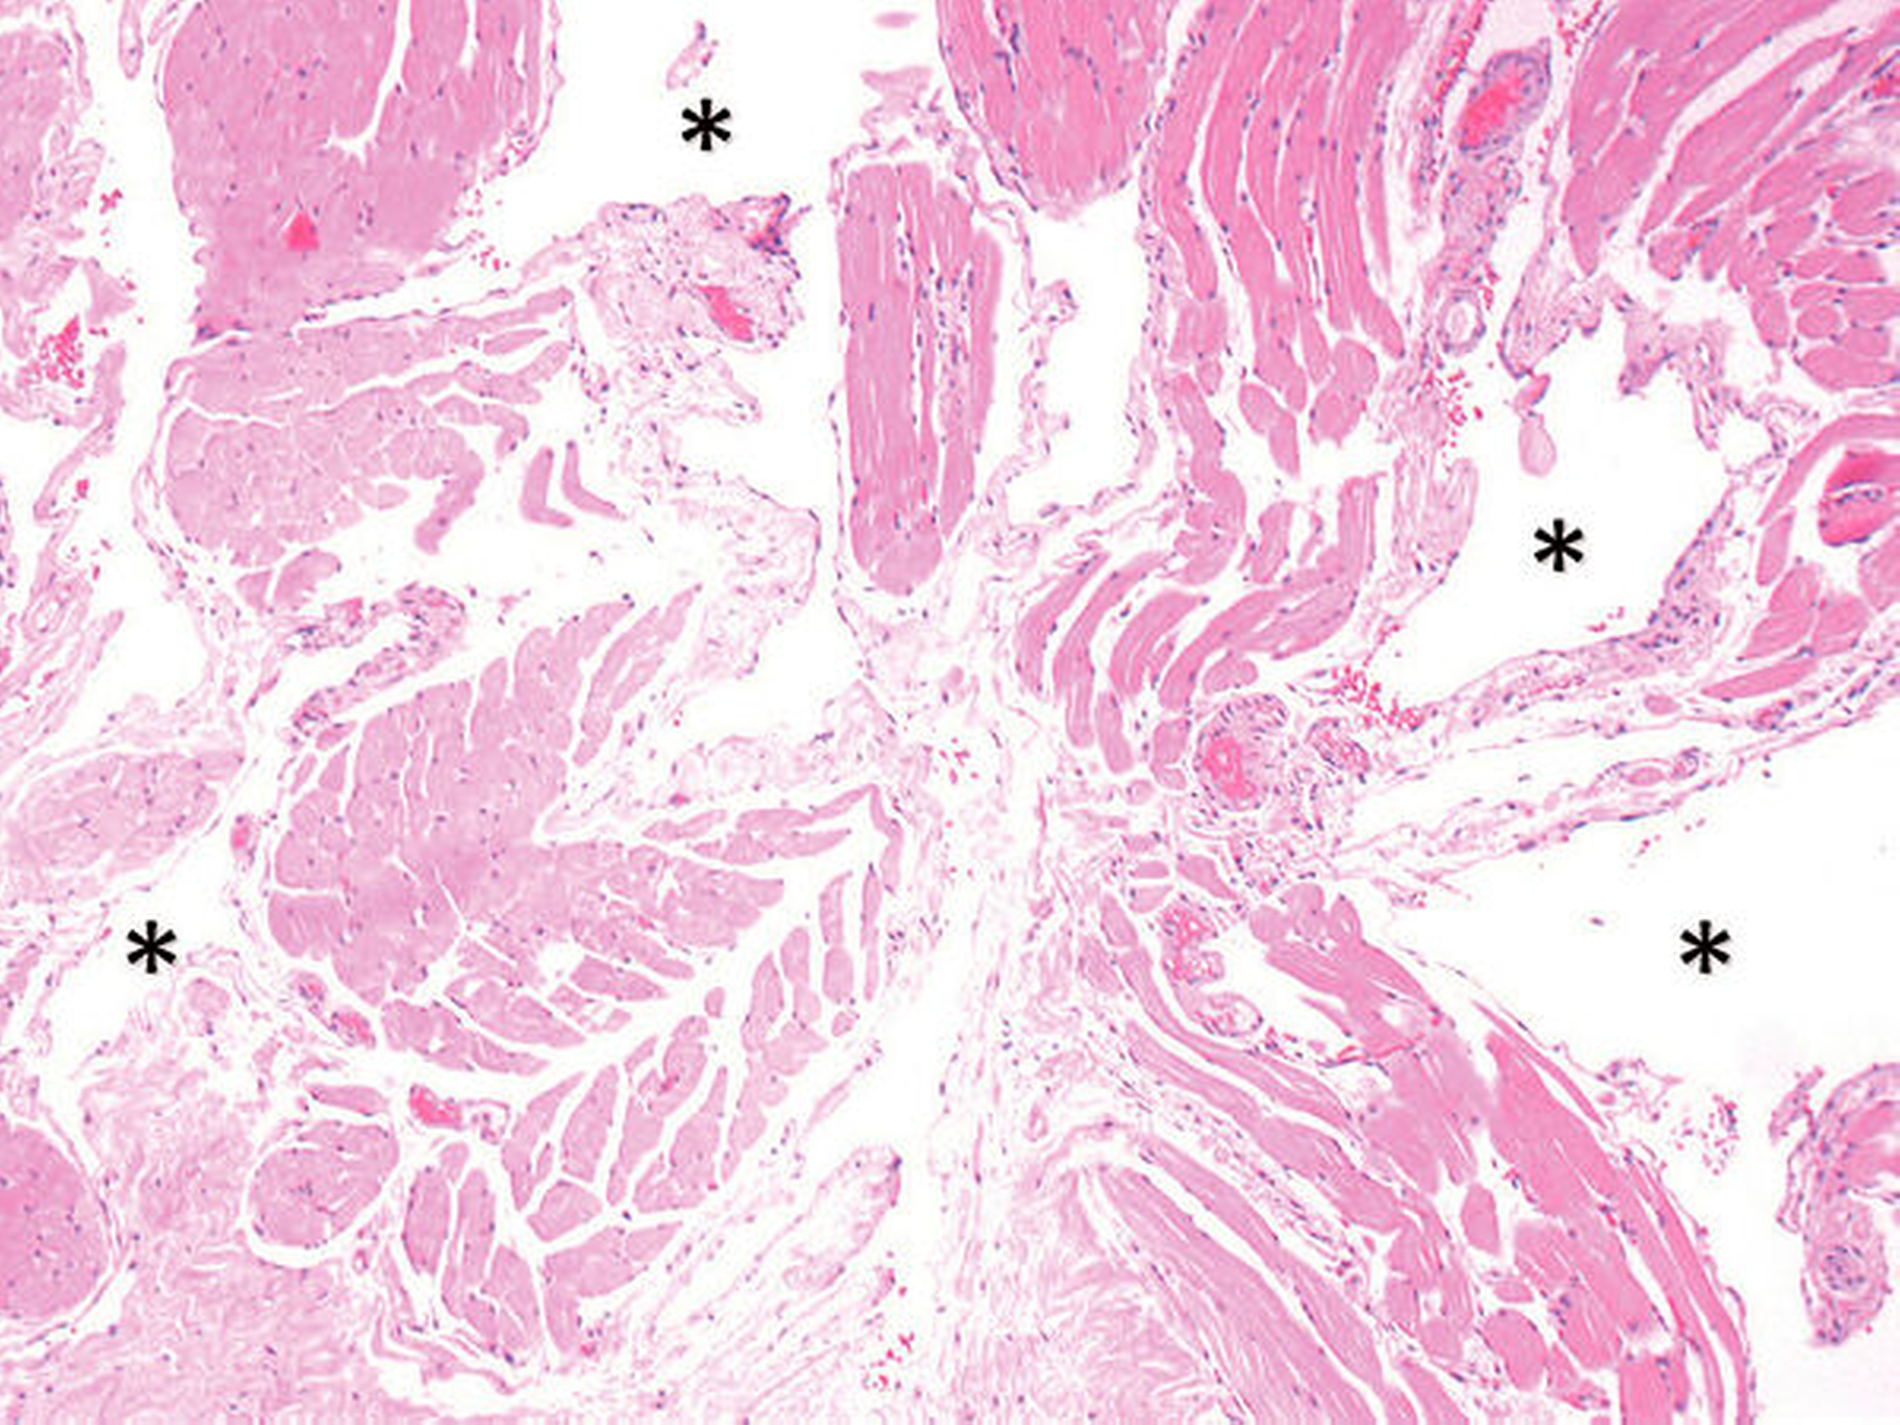

Aufgrund der akut vorherrschenden Perforationsgefahr mit daraus eventuell resultierender lebensbedrohlicher Blutung und der patientenseitig beschriebenen aktuellen Progredienz wurde die Indikation zur Operation gestellt. Unter stationären Bedingungen erfolgte die Exzision der vaskulären Anomalie (Abbildung 4a) mit primärer, lokal plastischer Deckung (Abbildung 4b) in Intubationsnarkose. Abbildung 5 zeigt das Exzidat. Histologisch wurde ein partiell regressiv verändertes, kavernöses Hämangiom mit intravaskulären Verkalkungen ohne Hinweis auf Malignität nachgewiesen (Abbildung 6).

Histologisch sind Hämangiome kapsellos und zeichnen sich durch zumeist venöse oder kapilläre hyperplastische Blutgefäße sowie – phasenabhängig – durch ihre erhöhte endotheliale Mitoserate aus. Dabei wird eine kapilläre von einer kavernösen Form unterschieden, wobei das kapilläre Hämangiom aus vielen kapillären Bündeln besteht, deren Endothelzellen ohne bindegewebige Zwischenschicht direkt aneinander liegen. Das kavernöse Hämangiom zeichnet sich hingegen durch große, dünnwandige Gefäße oder Sinusoide aus, die durch eine dünne bindegewebige Zwischenschicht voneinander getrennt sind [Kamala et al., 2014].